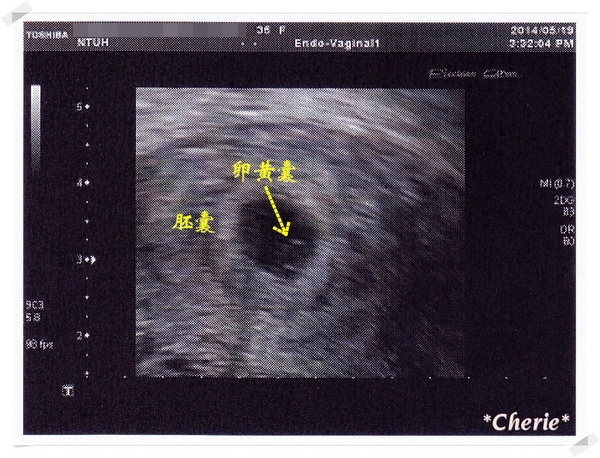

孕 初期 5w2d 與寶寶的第一次見面 Cherie 彩色棉花糖 痞客邦